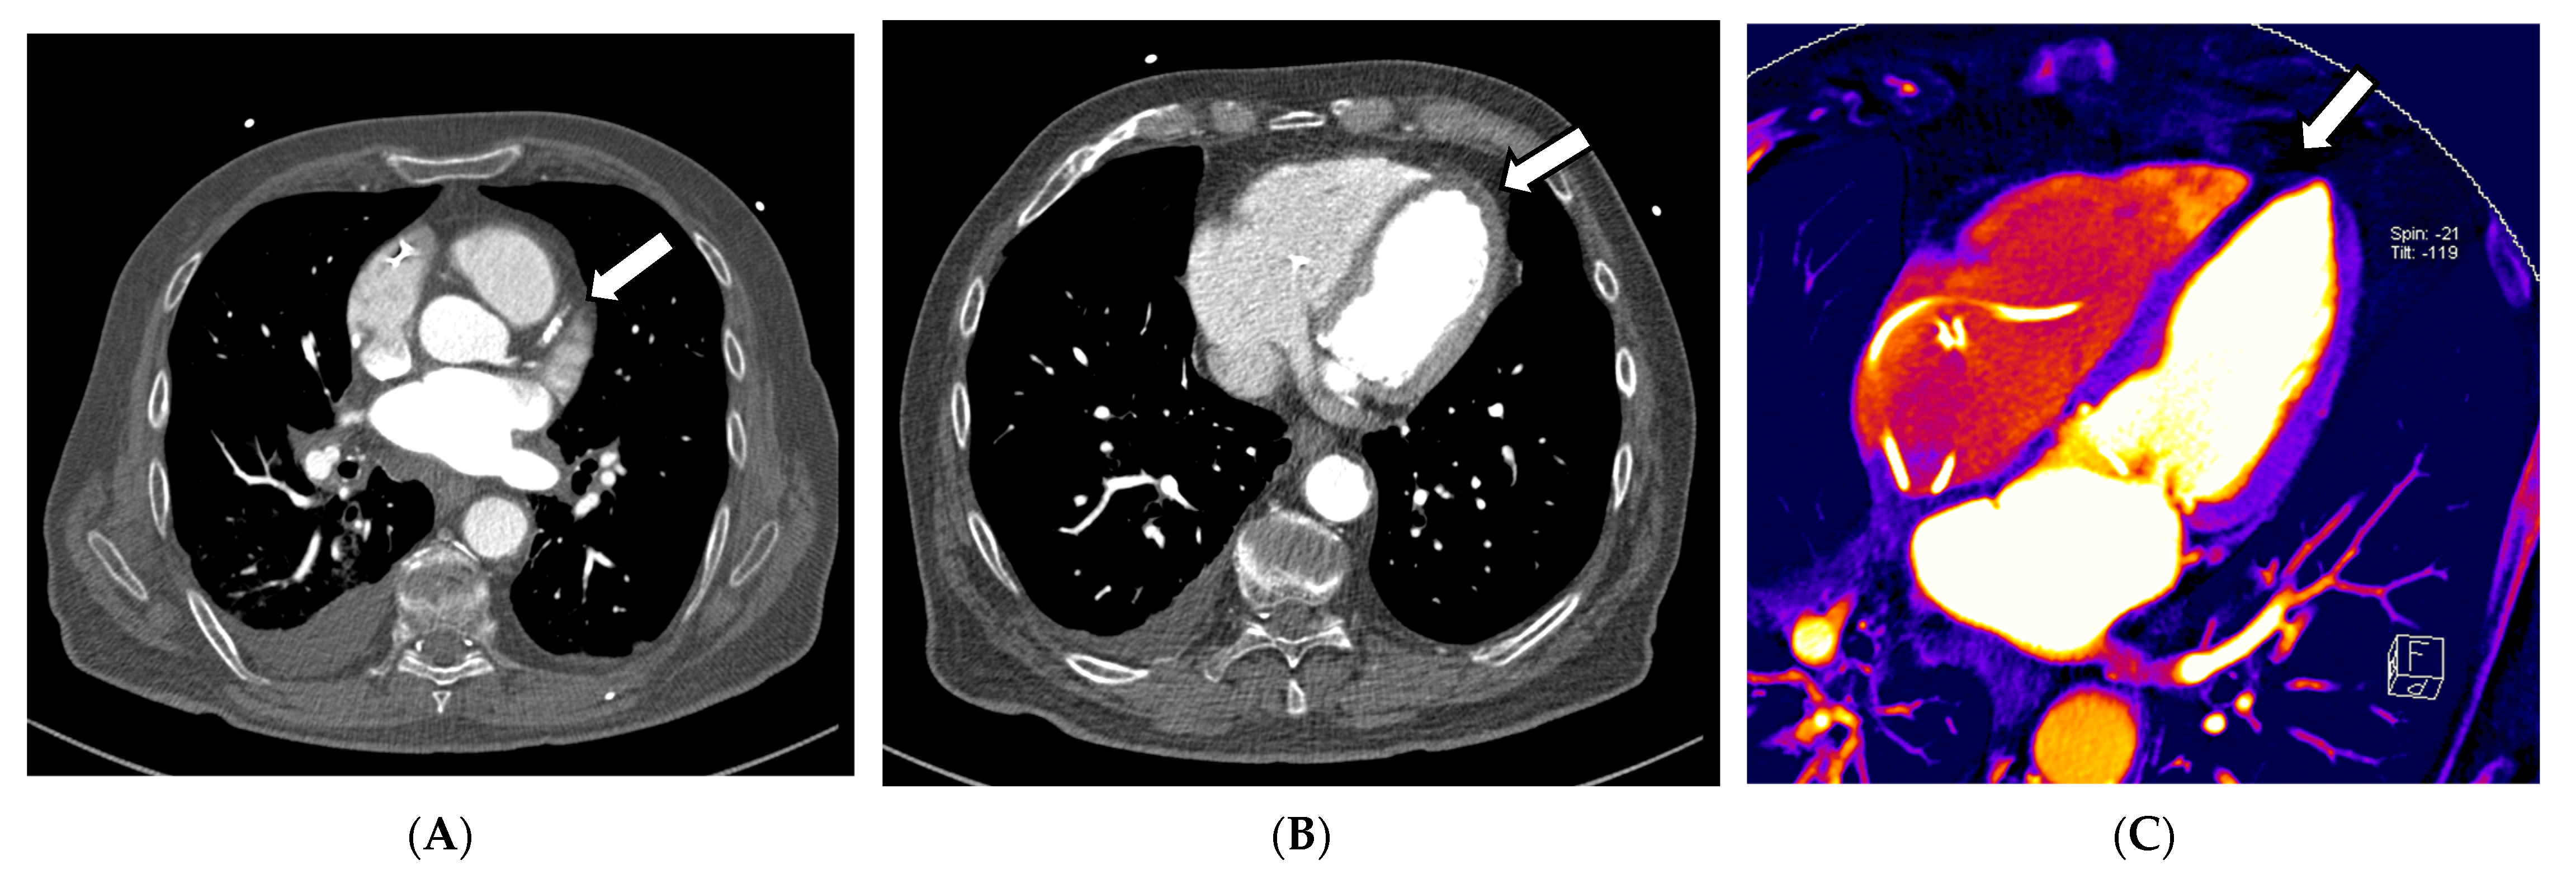

In this context, in addition to common CCTA, additional information on myocardial perfusion imaging (MPI), and thus, the functionality and prognosis of myocardial infarctions, can be derived according to Jin et al. (2016) [36]. This information can be derived from iodine images or maps, which are surrogate parameters of organ perfusion, by visualizing the amount of iodine from the contrast agent present. Kwan et al. (2021) describe that if a regional lower iodine attenuation is visible in the myocardium, it indicates myocardial infarction [36,57]. This is consistent with the method of creating iodine maps to indicate arterial lung embolism, in which the quality of DECT is essential, as the accuracy of iodine maps is directly related and proportional to the DE iodine, which is calculated by comparing the attenuation values of iodine at the two different energies. This ratio provides information about the iodine concentration within the scanned region. This means that the better the spectral separation of the high- and low-kV spectra, the less noise occurs, while the image quality of iodine maps improves, and likewise, the better the VNC images are that are created from the data. These two techniques, CCTA and myocardial perfusion, play a significant role in cardiovascular diagnostic imaging; some approaches combine both in one examination (see Figure 3A–D). Despite very promising results regarding specificity and sensitivity, false-positive CCTA MPIs can occur, which might be explained by possible artifacts from beam hardening or high iodine quantities in the heart, causing inaccurate perfusion maps [58]. As discussed above, the quality of the DECT examination is responsible for achieving a good DE iodine ratio. If the scan protocol, hardware, or patient positioning in the central FOV is insufficient, this can severely impact the image quality, thus affecting the reliability of the perfusion images, which limits the impact of MPI for clinical usage. According to Albrecht et al. (2018), the findings should be cautiously assessed and related to each patient’s clinical symptoms, similar to hybrid positron emission tomography and SPECT/CCTA studies. Still, it was proven that coronary artery CT of the heart using the latest generation MDCT has a diagnostic accuracy similar to that of invasive coronary angiography [58]. For the detection of chronic and acute abnormalities of the coronary arteries, an ECG-triggered CT of the heart can be highly accurate; however, such as in any CTA, the contrast can be insufficient due to several issues. One reason may be the insufficient concentration of iodine contrast in the vessel at the acquisition time. It can be an additional problem in systems with small detectors, which must acquire 2–3 different CT volumes in the diastole of heart action. The acquisition of a combined CT scan can take up to three heartbeats; thus, a short bolus can lead to missing the maximum contrast concentration in all or several volumes, leading to a decreased diagnostic validity of the study. In the context of coronary atherosclerosis, even small plaques can cause a difference in the perfusion of the myocardium. In conventional cardiac CT, blooming artifacts can lead to over- or after-subtraction techniques, even to underestimation of the obstruction of the lumen [57].

Figure 3.

Exemplary cardiac application of DECT in a patient admitted to the emergency chest pain unit suffering from acute angina pectoris symptoms with troponin and CK-MB elevation. The acquisition of a 120/80 kV third-generation dual-source DECT showed occlusion of the right interventricular artery (RIVA) in the CCTA (A). In the axial soft tissue kernel reconstruction, the interventricular septum and the myocardium of the left ventricle showed mild hypodensity at a closer look (B). Additionally, iodine perfusion maps were calculated from the data, revealing a myocardial perfusion deficit of the anterolateral wall and parts of the anterior septum (C–E). These findings correlate to signs of an anterolateral myocardial infarction, also reported in the ECG in the emergency room.

In the CADRADS 2 criteria for diagnosing coronary artery disease, four vulnerability criteria were described (low attenuation, positive remodeling, spotty calcification, and the napkin ring sign) [59]. These signs, directly correlated with a potential risk of myocardial ischemia, lead to an upgrade in the classification. Thus, it is clinically relevant to have a cardiac CT with high sensitivity and specificity [28,30].